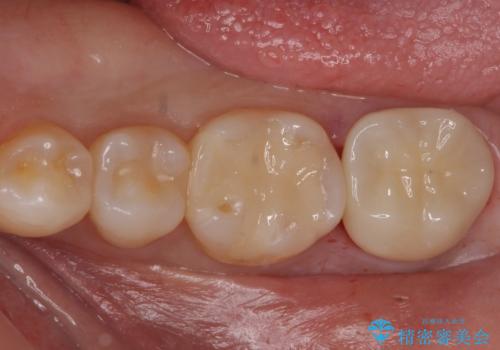

白い物で治療して欲しいとのことで、セラミックの詰め物だと詰め物の範囲が大きく、割れてしまう可能性があるので

ジルコニアクラウン(被せもの)で治療を行いました。

- 仮歯・ジルコニアクラウン 12.1万円費用は治療当時の料金となります

定期的なメンテナンスを行うことが大切です。